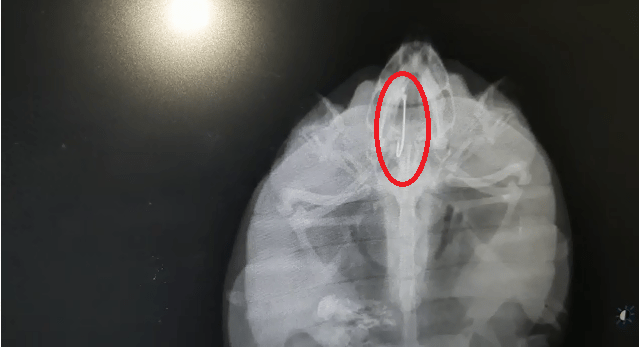

Professor Dr Indramani Nath of Veterinary Surgery and Radiology conducted X-ray to locate the position of the fishing hook, following which he was able to determine that it had not completely swallowed the fishing hook, and it was resting in its mouth. It took them 90 minutes to remove the hook.